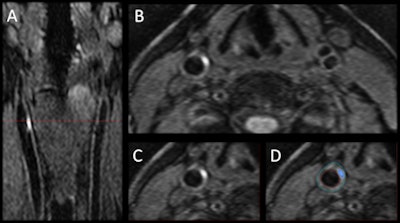

The participants underwent baseline 3D T1-weighted black-blood imaging for visualization of intraplaque hemorrhage, and 3D time-of-flight imaging to measure carotid artery vessel wall volumes and hemorrhage volumes.

"The major advantage of MRI is that it has high resolution and can distinguish the different components of plaque: not just intraplaque hemorrhage, but other features such as lipid, calcium, or fibrous tissue," Maraj added.

3D MRI revealed the presence of intraplaque hemorrhage in 37 patients (23%), with five individuals (3%) having hemorrhages in both carotid arteries. In addition, vessel wall volume in patients with carotid arteries positive for intraplaque hemorrhage was significantly larger than volume in those with no IPH.